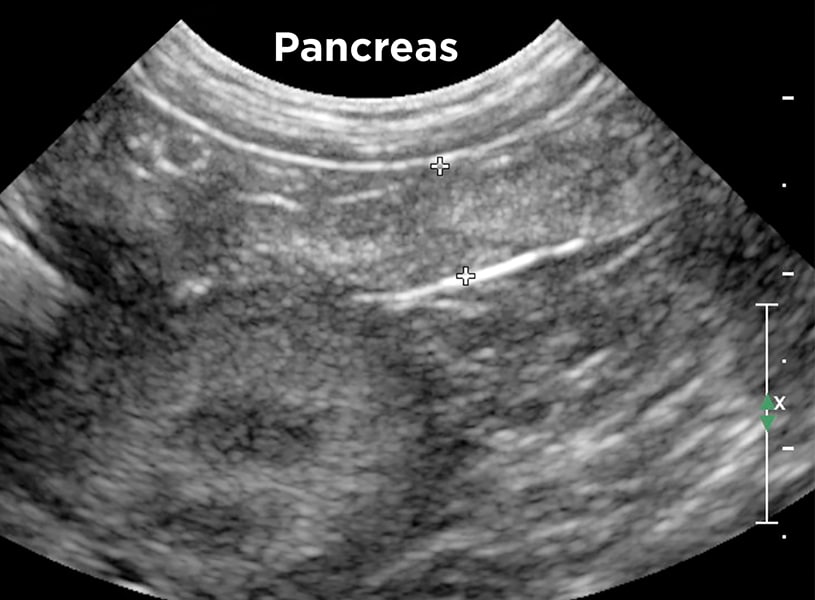

Pancreas

medial to the duodenum on right side

echogenicity similar to liver

Function:

- has exocrine and endocrine functions

- produces important digestive enzymes (exocrine)

- produces hormones and deposits them directly into the bloodstream